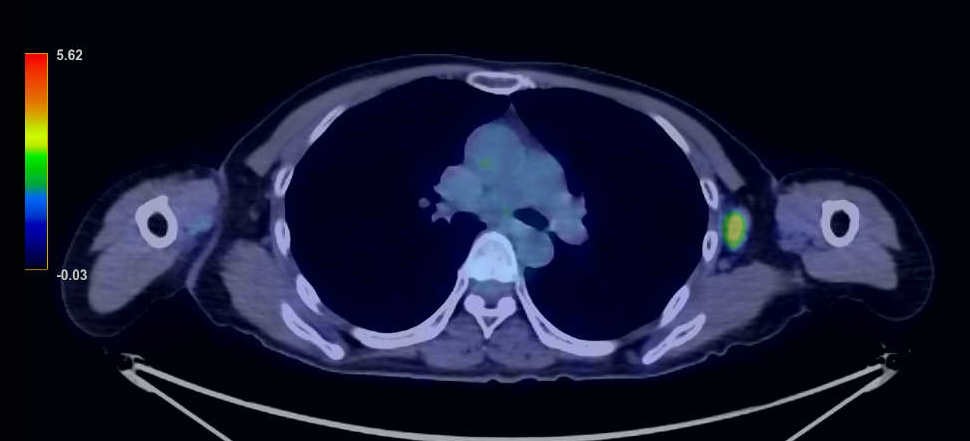

During a routine postoperative ultrasound examination 10 years after surgery, an enlarged left axillary lymph node measuring 2 cm in diameter was noted (Figure 1). A needle biopsy of the enlarged lymph node was performed, and metastatic recurrence of breast cancer was diagnosed. The histopathology of the needle biopsy showed highly attenuated expression of E-cadherin, which suggested the possibility of invasive lobular carcinoma. CT and PET/CT scans showed only enlarged left axillary lymph nodes and no distant metastasis (Figures 2 and 3).

Figure 3. PET/CT scan showing a left axillary lymph node with a maximum standard uptake value of 3.7. No accumulation is seen in other organs.